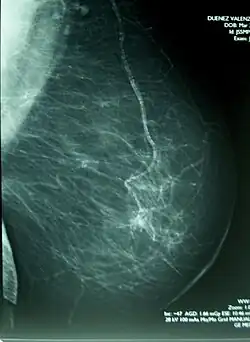

Mammographie oder Mammografie (von lateinisch mamma „Brust“ und -graphie) ist eine Methode zur Früherkennung von Brustkrebs (Mammakarzinom), der in den meisten Ländern häufigsten Krebserkrankung der Frau. Die Mammographie ist in erster Linie ein Verfahren der Radiologie zur Diagnostik der weiblichen, gegebenenfalls aber auch der männlichen Brust, und wird als Synonym für die Röntgenmammographie verwendet. Alternative bildgebende Verfahren sind die Mammasonographie, die Tomosynthese, die Magnetresonanz-Mammographie sowie die Brust-Computertomographie (Mamma-Computertomographie).

Die Untersuchung erfolgt an speziellen Röntgengeräten. Die angewendete Röntgenstrahlung ist eine weiche Strahlung mit einer Energie von ungefähr 25 bis 35 keV (Kiloelektronenvolt). In der Mammographie kommen praktisch kaum noch Film-Folien-Systeme, sondern hauptsächlich digitale Röntgengeräte zum Einsatz. Letztere teilen sich in Speicherfoliensysteme und Flachdetektorsysteme auf. Diese wiederum teilen sich auf in direkt digitale Detektoren, bei denen die Röntgenstrahlung direkt in ein elektrisches Signal umgewandelt wird und in indirekt digitale Detektoren, bei denen die Röntgenstrahlung erst in sichtbares Licht und dann in ein elektrisches Signal umgewandelt werden. Die Röntgenaufnahmen werden auf einer speziellen Mammographie-Befundstation betrachtet, welche sich im Wesentlichen durch zwei Graustufenmonitore mit jeweils 5 Megapixeln auszeichnet oder aber einen Graustufenmonitor mit mindestens 10 Megapixeln.

Jede Brust wird aus zwei, gegebenenfalls auch mehreren Richtungen aufgenommen. Die beiden am häufigsten und üblicherweise angewendeten Projektionen sind die cranio-caudale Abbildung (Röntgenbild der Brust von oben) und die MLO-Aufnahme (mediolateral oblique, Röntgenbild der Brust von der Mitte nach außen). Während der Aufnahme wird die Brust zwischen dem Objekttisch und einer Plexiglasplatte moderat komprimiert. Dies ist notwendig, um die Strahlendosis gering zu halten und die zu untersuchende Brustregion bestmöglich abzubilden. Die Untersuchung wird von einem Teil der Patientinnen als unangenehm empfunden.

Die weiche Strahlung führt zu kontrastreicheren Aufnahmen, als sie bei anderen Röntgenuntersuchungen mit harter Strahlung möglich wären. Mit der Untersuchung können kleine, nicht tastbare Gewebeformationen sowie Mikrokalk erkannt werden. Die Röntgenbilder werden durch den untersuchenden Arzt ausgewertet, wobei in den europäischen Screeningprogrammen die Doppelbefundung durch zwei Ärzte erfolgt. Hierbei können CAD-Systeme (Computer-assisted Detection) die Radiologen bei der Auswertung von Röntgenaufnahmen unterstützen.[3] Sie sind in den USA und den Niederlanden abrechnungsfähig.